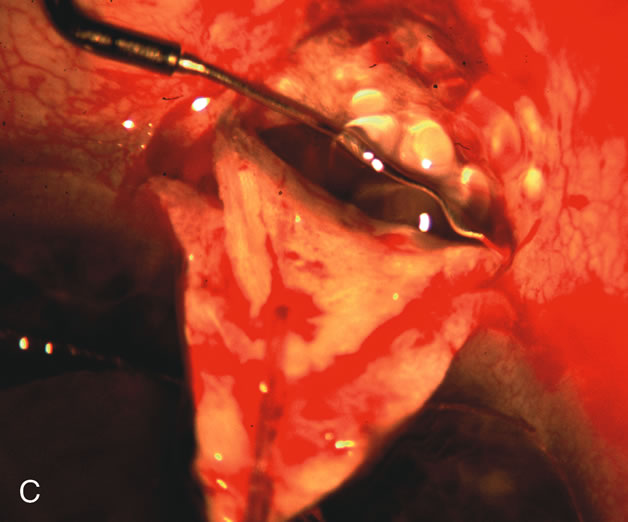

Nonpenetrating procedures as they exist today generally decrease postoperative complications but do not reduce IOP as successfully as trabeculectomy.140 The success rate also appears to be highly dependent on race, length of topical antiglaucoma therapy, and prior ocular surgery.141,142 Deep sclerectomy combined with phacoemulsification results in an IOP reduction similar to phacotrabeculectomy at one year with comparable visual outcome.143 Phacoviscocanalostomy lowers IOP by approximately 33%144 through either a one- or two-site approach145 (Fig. 4). Nonpenetrating procedures are in evolution, and their place in long-term glaucoma care is still unclear.

Fig. 4. Viscocanalostomy with deep sclerectomy and phacoemulsification. Nonpenetrating filtration procedures (NPFS) may be combined with phacoemulsification. Patients with mild disc damage and a history of limited topical drug therapy are the best candidates. Patients who require an IOP in the low teens are not good candidates for NPFS. By definition, NPFS is designed to lower IOP without penetrating into the anterior chamber, thereby avoiding the complications associated with trabeculectomy. Viscocanalostomy is intended to allow aqueous to percolate through a trabeculodescemetic membrane into a subscleral cavern created by the deep sclerectomy. The aqueous diffuses from the cavern into the dilated ostia of Schlemm's canal and into the episcleral venous plexus. A. Fashion a uniform 300-micron superficial scleral flap 1 mm into clear cornea. B. Construct a second 600-micron deep flap that facilitates the unroofing of Schlemm's canal, seen as the darker area. C. Use viscoelastic to dilate the ostia of Schlemm's canal. The major problem with viscocanalostomy is the eventual closure of the ostium decreasing flow to the episcleral plexus. D. Dissect the deep flap anteriorly into clear cornea creating the trabeculodescemetic membrane. This membrane is clearly seen between the scleral spur and the bend of the deep flap. The integrity of this membrane ensures the nonpenetrating portion of the surgery. Another problem with NPFS is the eventual fibrosis of this initially transparent membrane requiring goniopuncture. E. Deep sclerectomy gets its name from removal of the deep flap. Removal of this flap creates the potential subscleral space for accumulation of aqueous before it enters Schlemm's canal and exits the episcleral venous plexus. After removal of the deep flap, the superficial flap is sutured into place and conjunctiva closed. Approximately half of these procedures develop a shallow bleb.